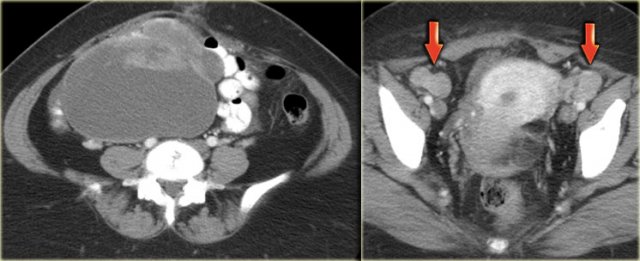

Ultrasound shows a complex solid-cystic mass in the left ovary, and another, very large complex solid-cystic mass in the right hemi-pelvis.

CT of the same patient shows a complex solid-cystic mass with thick, enhancing septations in the right ovary.

These findings are very suspicious for a malignant cystic neoplams.

There is also bilateral lymphadenopathy (arrows).

Pathology showed a serous ovarian cystadenocarcinoma.

CT of the same patient confirms large bilateral complex solid-cystic lesions, bulging into the abdomen.

The purpose of the CT is not to confirm what was already known from the ultrasound, but to stage disease.

For this patient the relevant findings are on the image on the left.

There is a peritoneal implant.

The tumor was resected and pathology showed this was an endometrioid ovarian carcinoma.